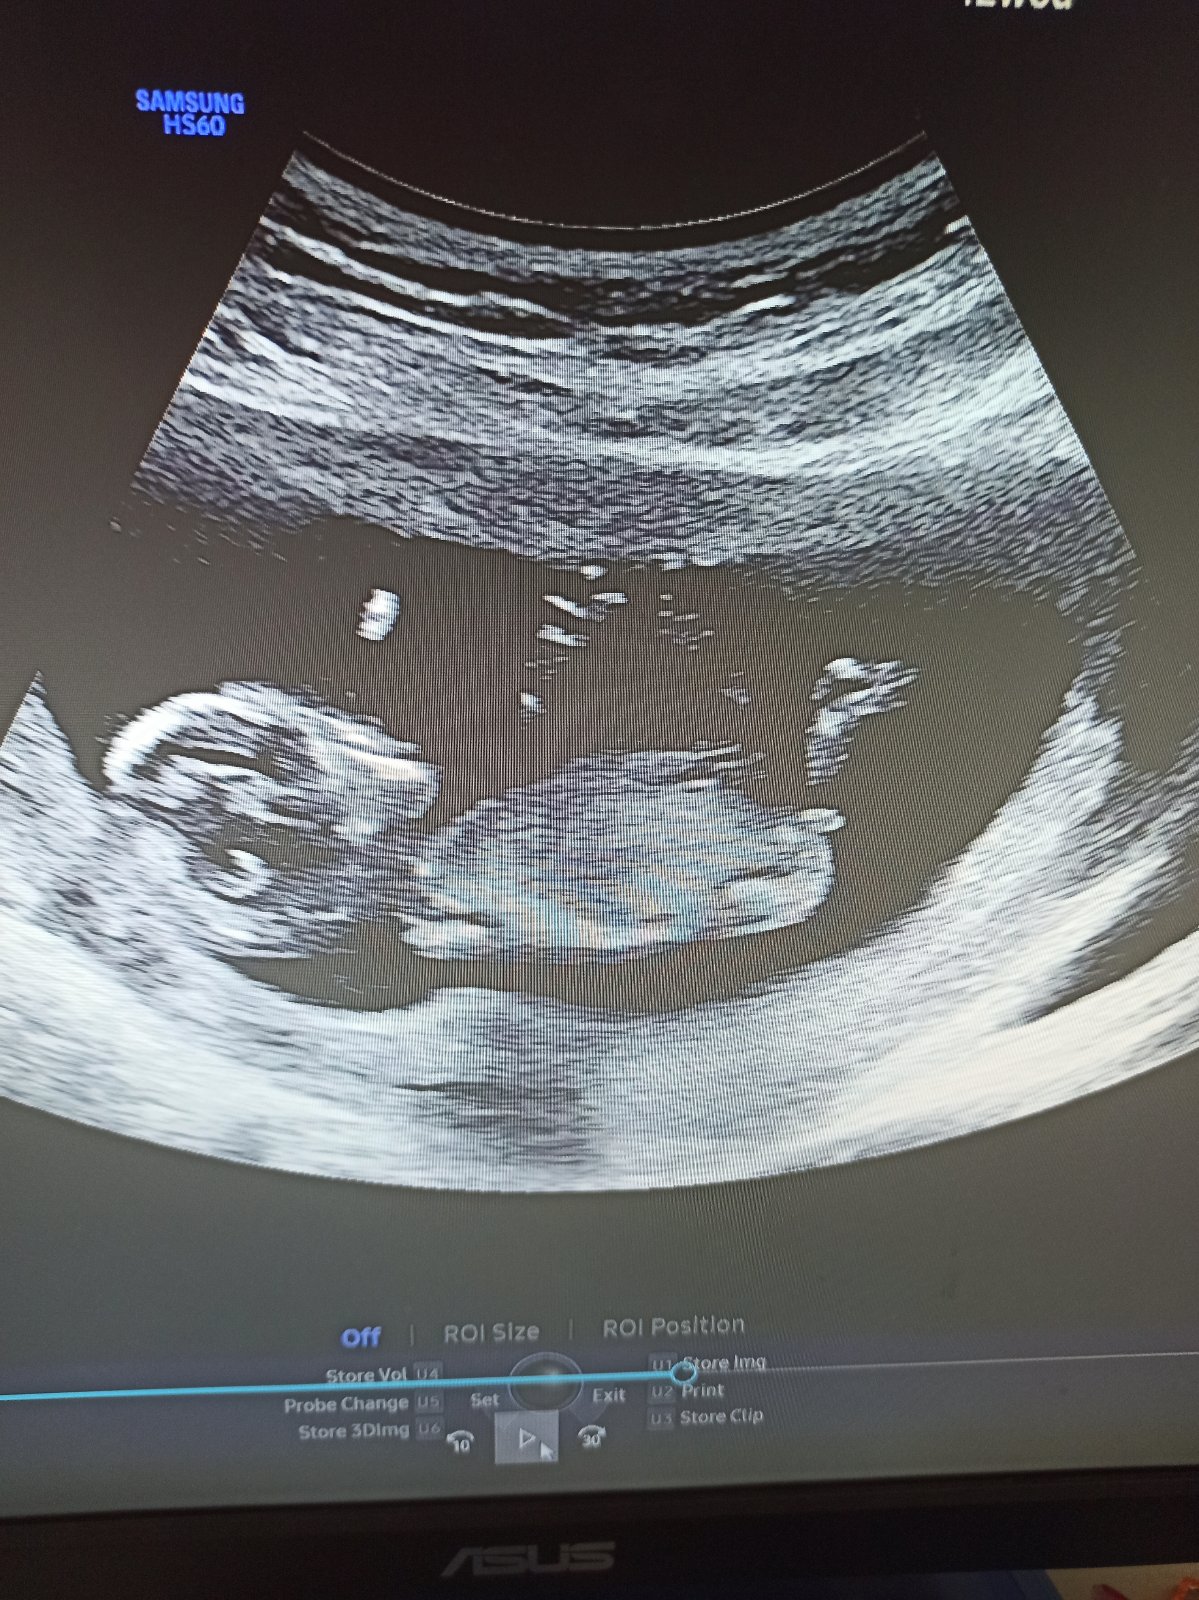

Dobrý den, oživuji diskuzi ❤️ 11tt, je to jen screenshot z videa které jsem si natočila na mobil, tak bůh ví, zda jsem to cvakla v dobrou chvíli a není to klamavé 😄 Co myslíte? Do prenatalu jdeme až 6.11. a já mám pocit že prasknu nedočkavostí, jsem zvědavec hrozný 🙈 Toť otázka - pohlavní hrbolek, nebo jsou to kulky, nebo konec kostrče? Co myslíte, jen tak pro srandu? Přáli bychom si holku, ale kdyz jsem videla prvni pohyby na UTZ v 11+1, tak jsem si uvědomila že ať bude co bude, budu mimi milovat uplne stejne bez rozdílu ❤️ Je to mazec!!